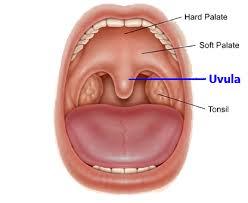

Oral Cavity (Buccal)

8

Hard Palate

9

Soft Palate

10

Rugae of the Hard Palate

11

Vestibule

12

Uvula